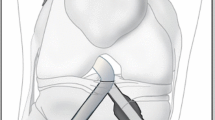

A sequential flexion of finite element model (ACL reconstructed knee model) was reproduced at four different angles (0°, 45°, 90° and 135°) as the femur was moved to each flexed position according to a 3D coordinate system based on the fixed tibia. Meanwhile, stress concentration and its maximum value were monitored in the lateral femoral condyle of the femur around the femoral tunnel (Fig. 2).

A sequential flexion of ACL reconstructed knee model was reproduced at four different angles (0°, 45°, 90° and 135°) as the femur was moved to each flexed position according to a 3D coordinate system based on the fixed tibia. Meanwhile, the stress concentration and its maximum value were monitored in the lateral femoral condyle around the femoral tunnel